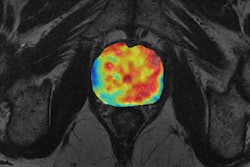

The research stems from an initial collaboration between University Hospital Basel and 4Quant on a project exploring nasopharyngeal cancer, a rare cancer worldwide but unusually common in southern China. Early detection plays a crucial role in successful outcomes with nasopharyngeal cancer. A number of different treatment options are available with varying levels of side effects; both staging and grading are critical for optimizing patient care, according to the researchers, who shared their work in a poster presentation at RSNA 2016.

In the hope of finding tumors and predicting outcomes, the team sought to build a deep-learning model using 12,000 images from head MR examinations. First, the MR images were preprocessed through two different neural networks: a "neural image sorter" and a "neural position estimator." The 20-layer neural image sorter created an estimate of the type of image being input, while the 20-layer neural position estimator helped to pinpoint the position of the image within the frame, according to the group.

In testing, the researchers found their deep-learning model turned in a very strong performance in detecting nasopharyngeal cancer and measuring tumor features. The model's tumor volume calculations had a 96% correlation with the radiologist's calculations.